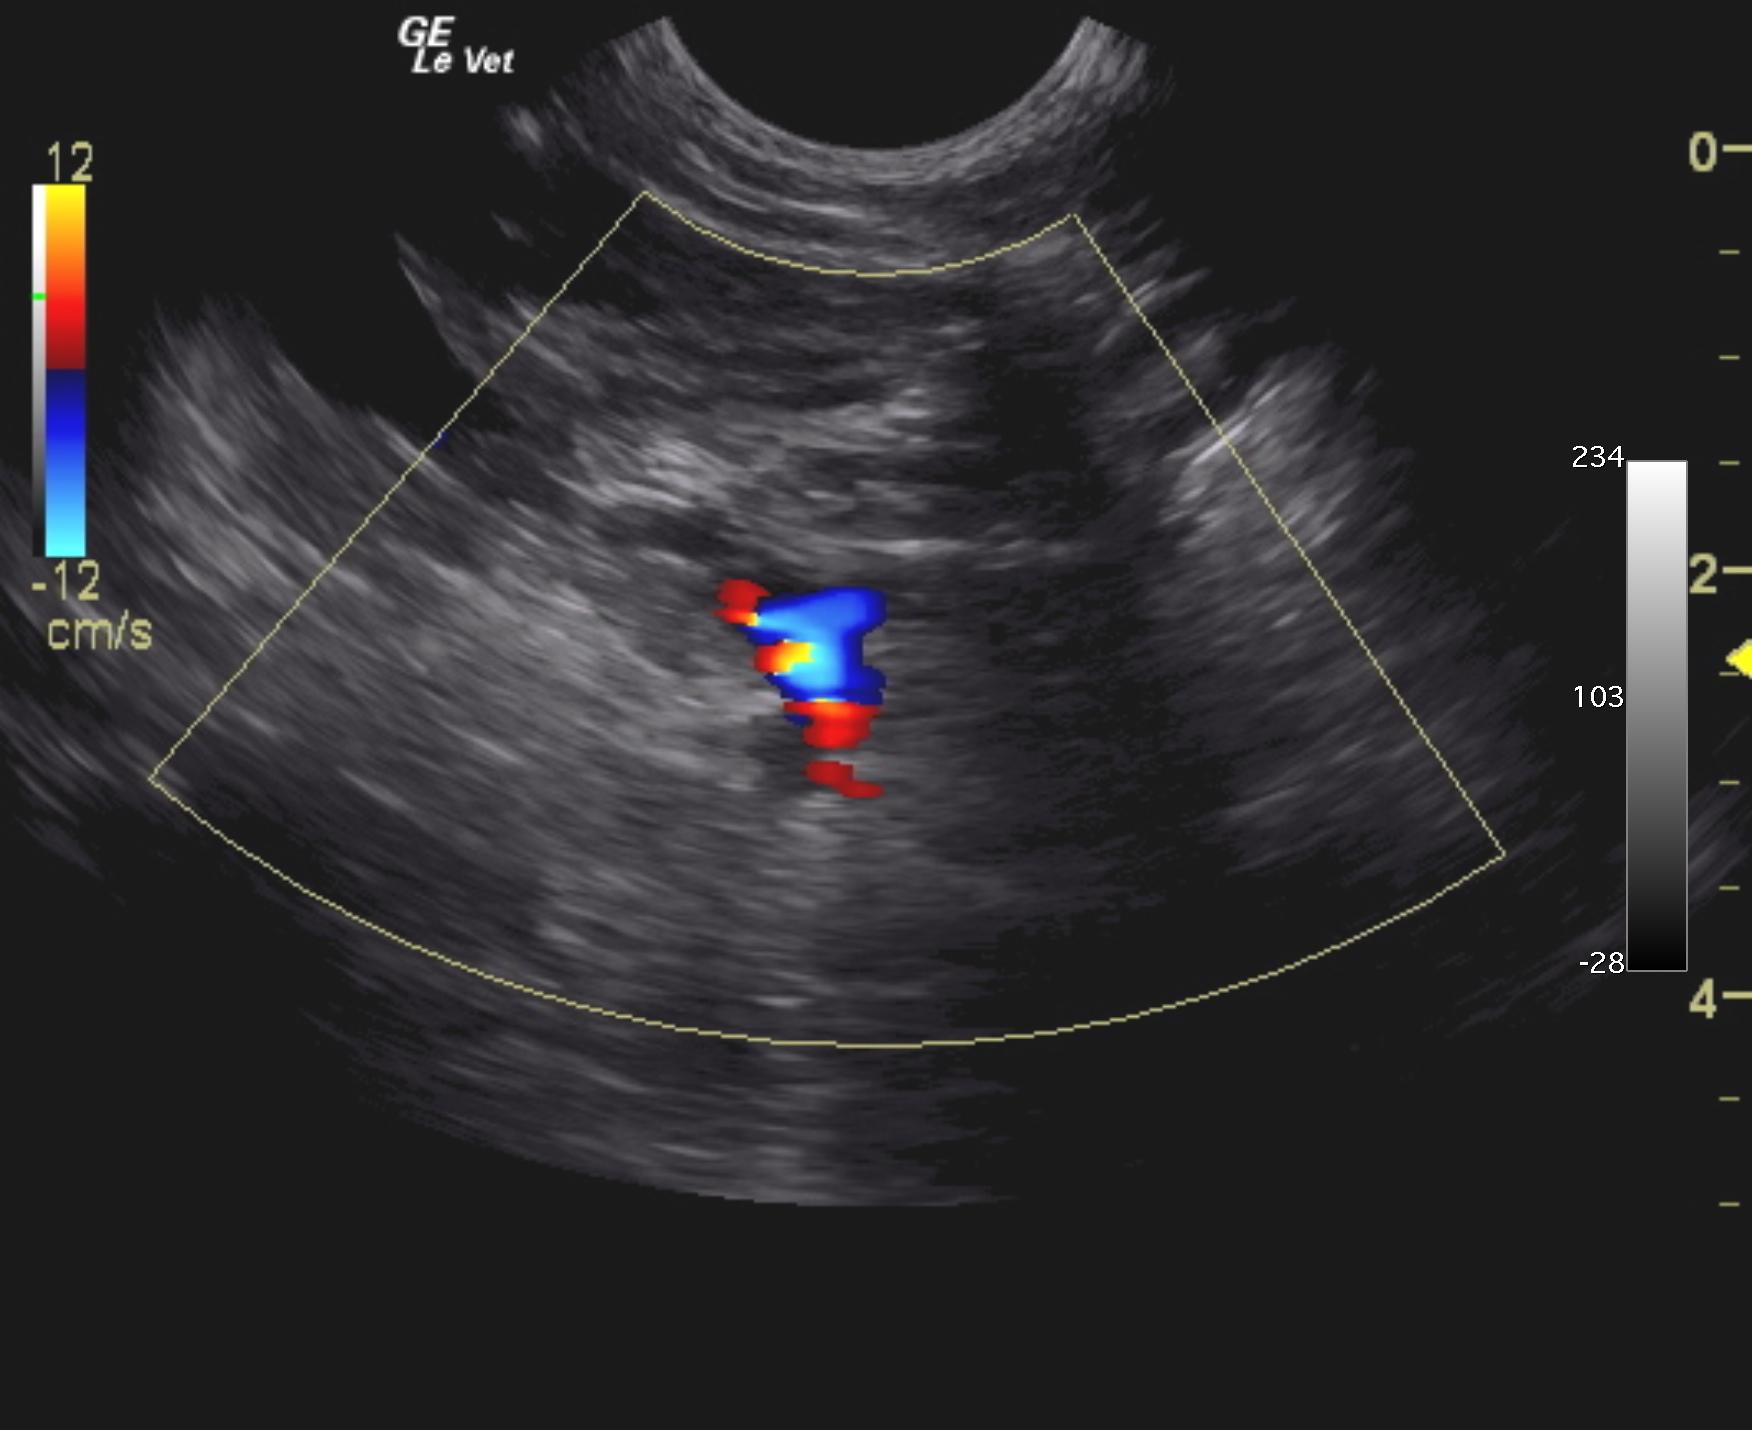

Extrahepatic portosystemic shunt was noted in this patient and measured 0.45 cm in width. The portal vein prior to the shunt measured 0.39 cm and post shunt measured 0.28 cm. This is most consistent with splenocaval shunt. The vena cava prior to the shunt entry measured 0.6 cm and the aorta measured 0.64 cm. The extrahepatic shunt passed dorsally and measured from 0.6 to 1.0 cm in width and entered into the vena cava dorsal ventrally prior to the diaphragm. The vena cava measured 1.0 cm at that point. The liver was subnormal in size and mildly coarse in architecture. The gallbladder was unremarkable.